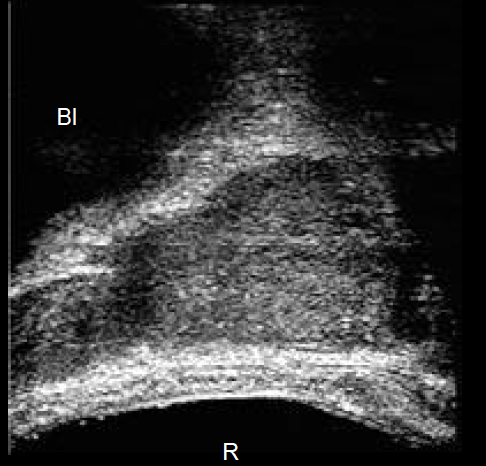

what type of exam is this?

transabdominal, transverse